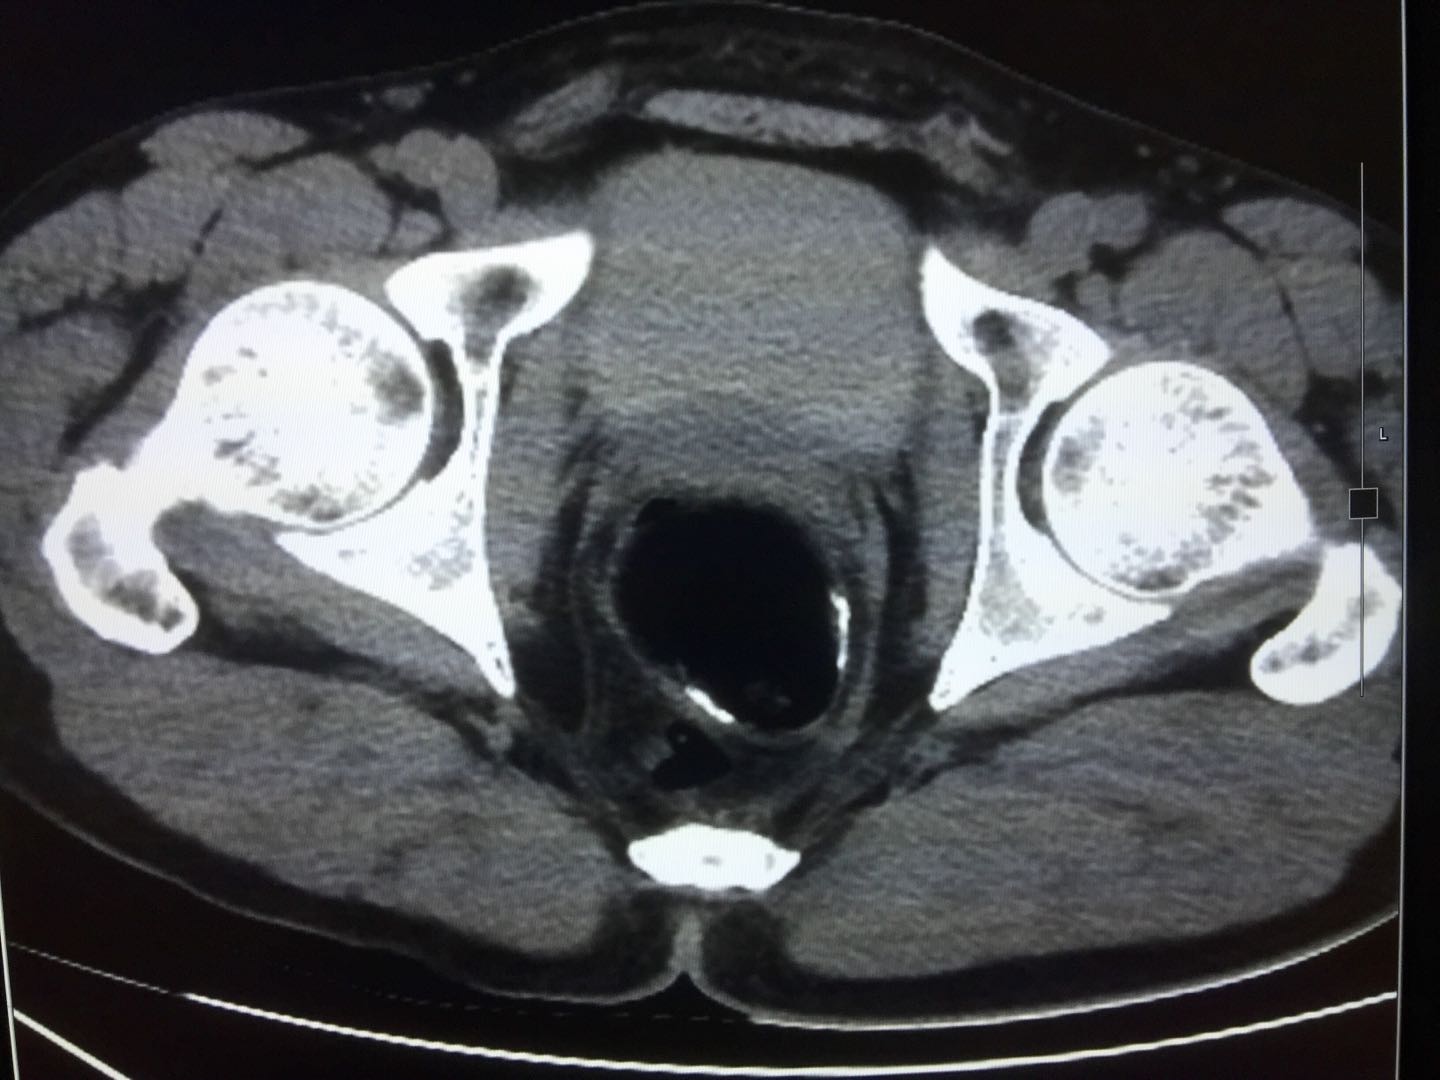

2020.10.16左肝部分切除术后52周复查,CEA 0.69ng/ml。

腹部MRI:肝S4部分切除术后改变。胸部及盆腔CT未见异常。

图片15. 左肝部分切除+肝门淋巴结清扫术后52周,腹部MRI

图片16.原发灶根切术后66周,盆腔CT

评价结果:NED状态2020.10.31左肝部分切除术后52周,NGS检测血液ctDNA结果:血液TMB为0,与腹部MRI图像吻合。